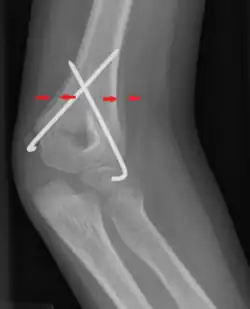

| Periosteal reaction on a healing supracondylar fracture | |

A periosteal reaction is the formation of new bone in response to injury or other stimuli of the periosteum surrounding the bone.[1] It is most often identified on X-ray films of the bones.

A periosteal reaction can result from a large number of causes, including injury and chronic irritation due to a medical condition such as hypertrophic osteopathy, bone healing in response to fracture, chronic stress injuries, subperiosteal hematomas, osteomyelitis, and cancer of the bone. It may also occur as part of thyroid acropachy, a severe sign of the autoimmune thyroid disorder Graves' disease.

The morphological appearance can be helpful in determining the cause of a periosteal reaction (for example, if other features of periostitis are present), but is usually not enough to be definitive. Diagnosis can be helped by establishing if bone formation is localized to a specific point or generalized to a broad area. The appearance of the adjacent bone will give clues as to which of these is the most likely cause.

Appearances include solid, laminated, spiculated, and the Codman triangle.[4]